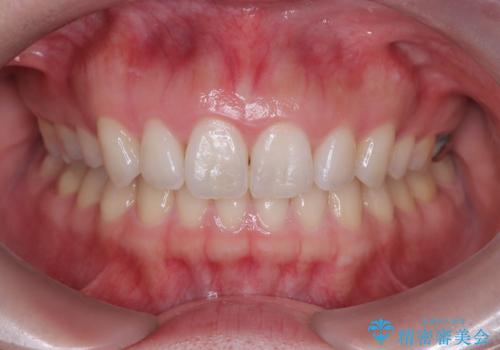

抜歯矯正をインビザラインで実現

- 患者様は、上下顎の歯列不正と前歯部の突出感を主訴としてご来院されました。診断の結果、上顎左右第一小臼歯を抜歯することでスペースを確保し、歯列全体を整える方針としました。本来はワイヤー矯正が推奨されるケースですが、患者様のご希望により、透明なマウスピース型矯正装置「インビザライン」を使用した治療計画を立案しました。治療期間は約3年で、奥歯の噛み合わせを維持しながら、徐々に前歯の位置を整えました。

インビザラインは見た目の目立ちにくさと取り外しが可能な点がメリットですが、複雑なケースでは治療計画の精密さが求められます。本症例では奥歯の噛み合わせが崩れないよう注意を払いながら、マウスピースの交換タイミングを細かく設定しました。患者様には装着時間を守っていただくことが重要で、1日20時間以上の装着が必須です。また、抜歯部位のスペースを閉じる過程で、歯の動きが停滞しやすい時期もあるため、定期的なチェックを通じて治療が順調に進むよう管理しました。